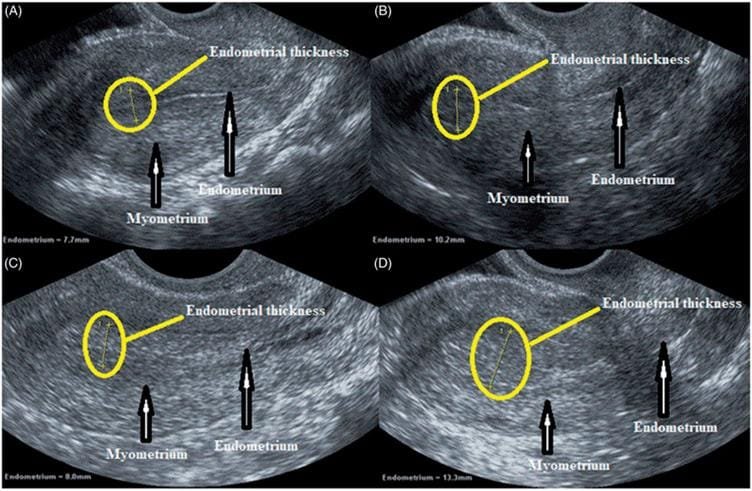

Image Source Credit : https://www.researchgate.net/figure/Ultrasound-scanning-sonographic-of-the-endometrial-thickness-measurement-A_fig7_337682120

✔ The uterine lining (endometrium) must be thick and healthy

In this process, Estrogen acts like the fertilizer, working to thicken the lining of your uterus so it becomes a soft, welcoming place. Once the lining is thick enough, Progesterone acts like a protective blanket, making the lining receptive and stabilizing it to support the embryo.